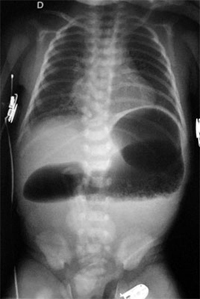

Hi sorry the humira has not worked but stay POSITIVE i had a right hemi the first time around in 93 i had open surgery and stayed in hossy about 2 weeks but that was because i was so underweight the recovery and pain relief was ok but is much better these days like Nanners said walk as soon as you can as this will make you recover quicker and stop you from getting chest infections it was the. Estenosis congénita de colon OBSERVACIÓN CLÍNICA Varón de dos meses que ingresó por un cuadro de vómitos, estreñimiento de 48 h de evolución y decaimiento Los padres referían encontrarle más irritable, aunque mantenía el apetito y estaba afebril Nacido de embarazo y parto controlados, eliminó me. A colon stricture is a narrowing of part of the colon The reduction in the diameter of the colon can lead to an impaction, where fecal material builds up behind the stricture because it cannot pass through Some patients with colon strictures may be unaware of the condition, while others can develop symptoms like constipation and abdominal.

Las atresias del colon (intestino grueso) son muy raras Síntomas La estenosis puede ser única o múltiple y su localización preferente es el íleon El síntoma predominante que habitualmente aparece es el dolor abdominal tras la ingesta, normalmente localizado en la zona derecha del abdomen, acompañado frecuentemente de náuseas. Thomas C Moore, Atresia of the colon at the splenic flexure with absence of the distal colon and ischemic destruction of the proximal colon, Journal of Pediatric Surgery, /S(78)X, 13, 1, (90), (1978). Spinal stenosis is a condition in which your spinal canal narrows It may cause back pain and other nerverelated problems With proper exercise and treatment, you can reduce its effects.